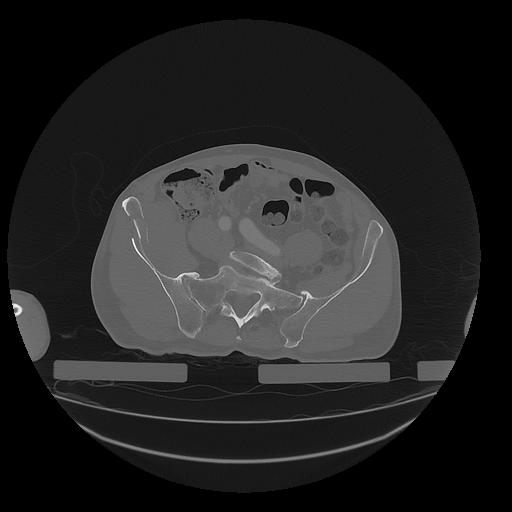

31 PULMON,CE,Vol,1.0,PULMON,,